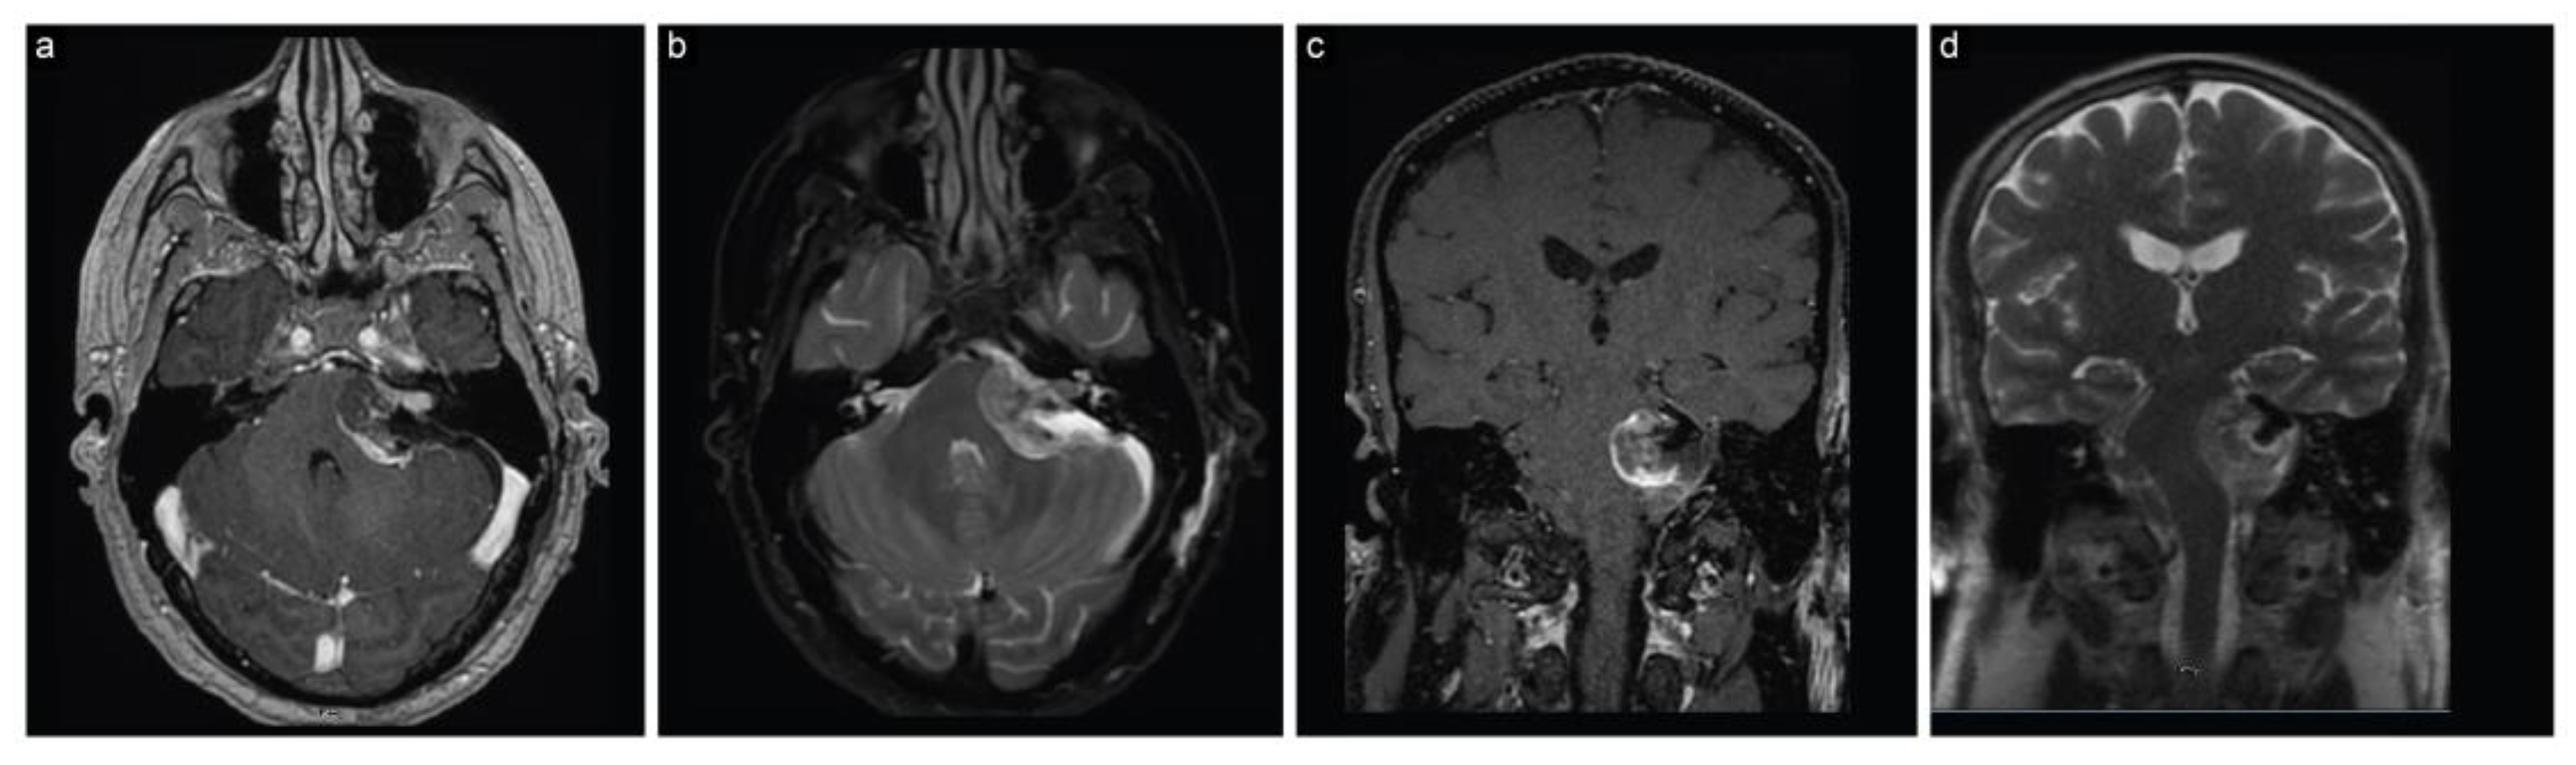

The patient immediately had a cranial MRI that displayed a sizeable (4 cm × 3.5 cm × 3.3 cm) left CPA lesion, consistent with a vestibular schwannoma (Figure 1). The lesion caused marked compression on the brainstem and fourth ventricle, resulting in hydrocephalus.

Figure 1.

Case 1, preoperative neuroimaging. (a) Axial T1-weighted postcontrast, (b) axial T2-weighted, (c) coronal T1-weighted postcontrast, and (d) axial T2-weighted MRI scans show a large CPA lesion suggesting a vestibular schwannoma along with hydrocephalus.